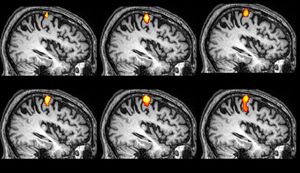

For victims of psychological trauma, the challenge of suppressing painful memories may be rooted in the wiring of the brain, an ongoing study revealed at the RSNA conference Wednesday.